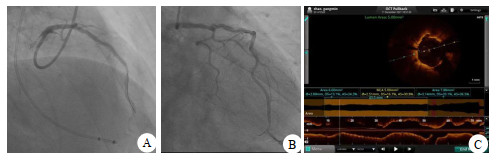

病例2,女,61岁。持续性心前区疼痛52 h,加重15 h,心电图提示:前壁、下壁ST-T改变(图 5)。cTnI 19.25 ng/mL,CK-MB 98.2 ng/mL(图 6),以非ST段抬高型心肌梗塞收住。评估后急诊PCI示罪犯血管OM 100%(图 7A),打通后置入2.25 mm×31.00 mm支架,PDA起始部95%狭窄(图 7B),FFR 0.78,LAD中段狭窄70%(图 7C),FFR 0.84(阴性),于PDA放置2.75 mm×29.00 mm支架,OCT测定支架远端膨胀不全,近端贴壁不良(图 8A),分别后扩球囊反复扩张,OCT再次检查无膨胀不全及贴壁不良现象(图 8B),FFR 0.92(图 8C),心肌酶趋势如图 6所示。

| A为OM 100%为罪犯血管;B为PDA起始部95%,FFR 0.78;C为LAD 75%,FFR 0.84 图 7 病例2的冠脉造影检查结果 |